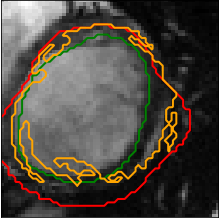

The Dice Metric (and the conformity coefficient) is our measure of performance on the online dataset that we are using as a validation dataset. Figure 5 shows the inferred shape (contour mask) when using a deeper model (two convolutional layers instead of one), a larger model (200 filters instead of 100), a model with ReLu activations and a last one with max pooling (instead of average pooling).

Customizing the loss of our neural network can totally change the performance of our approach in both ways [9]. Let’s recall that the method uses a customized loss for the two stacked autoencoder (weighting between Mean Square Error (MSE), regularisation and Kullback-Leibler (KL) divergence) in the unsupervised learning step and a regular MSE for the last fully connected layer in the supervised learning step. We test another alternative where all the losses are MSE and plot the contours from the manually segmented LV, the prediction with and without active contour models in Figure 6. As we can see, the contour is smoother and seems to fit the ground truth while having a meaningful shape (not shrinking or leaking or irregularities).

Even if we did not implement the geometric algorithm (level-set method) of the Deformable Models, we used the snakes approach with active contour models [10]. We thus smoothed the contours for both the prediction using customized and MSE losses and the one using only MSE losses. The prediction we finally achieve can be very much encouraging with the modified loss of the stacked Auto-Encoder as it is illustrated in Figure 7.